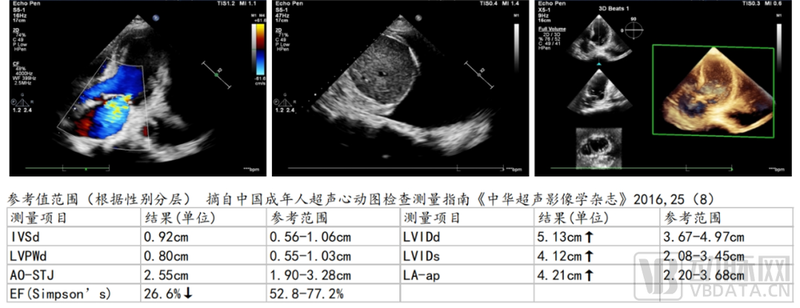

入院检查:心电图提示:窦性心动过速,前壁r波递增不良伴ST段轻度压低。心超提示:左室射血分数正常下限(LVEF 51.2%),左室心肌节段性运动异常。血液学检查提示:WBC 26.3x10^9/L,Hb 64g/L,肌酐271.5umol/L(估算eGFR 14ml/min),TnT 2.45ng/mL,NT-proBNP 1081.2pg/mL。

病情变化:患者入院后优化药物治疗效果欠佳,动态监测心肌酶谱提示TnT下降后又呈上升趋势,LVEF急转直下,下降至26.6%,BNP>5000pg/mL,病情危重,需紧急明确冠脉情况。